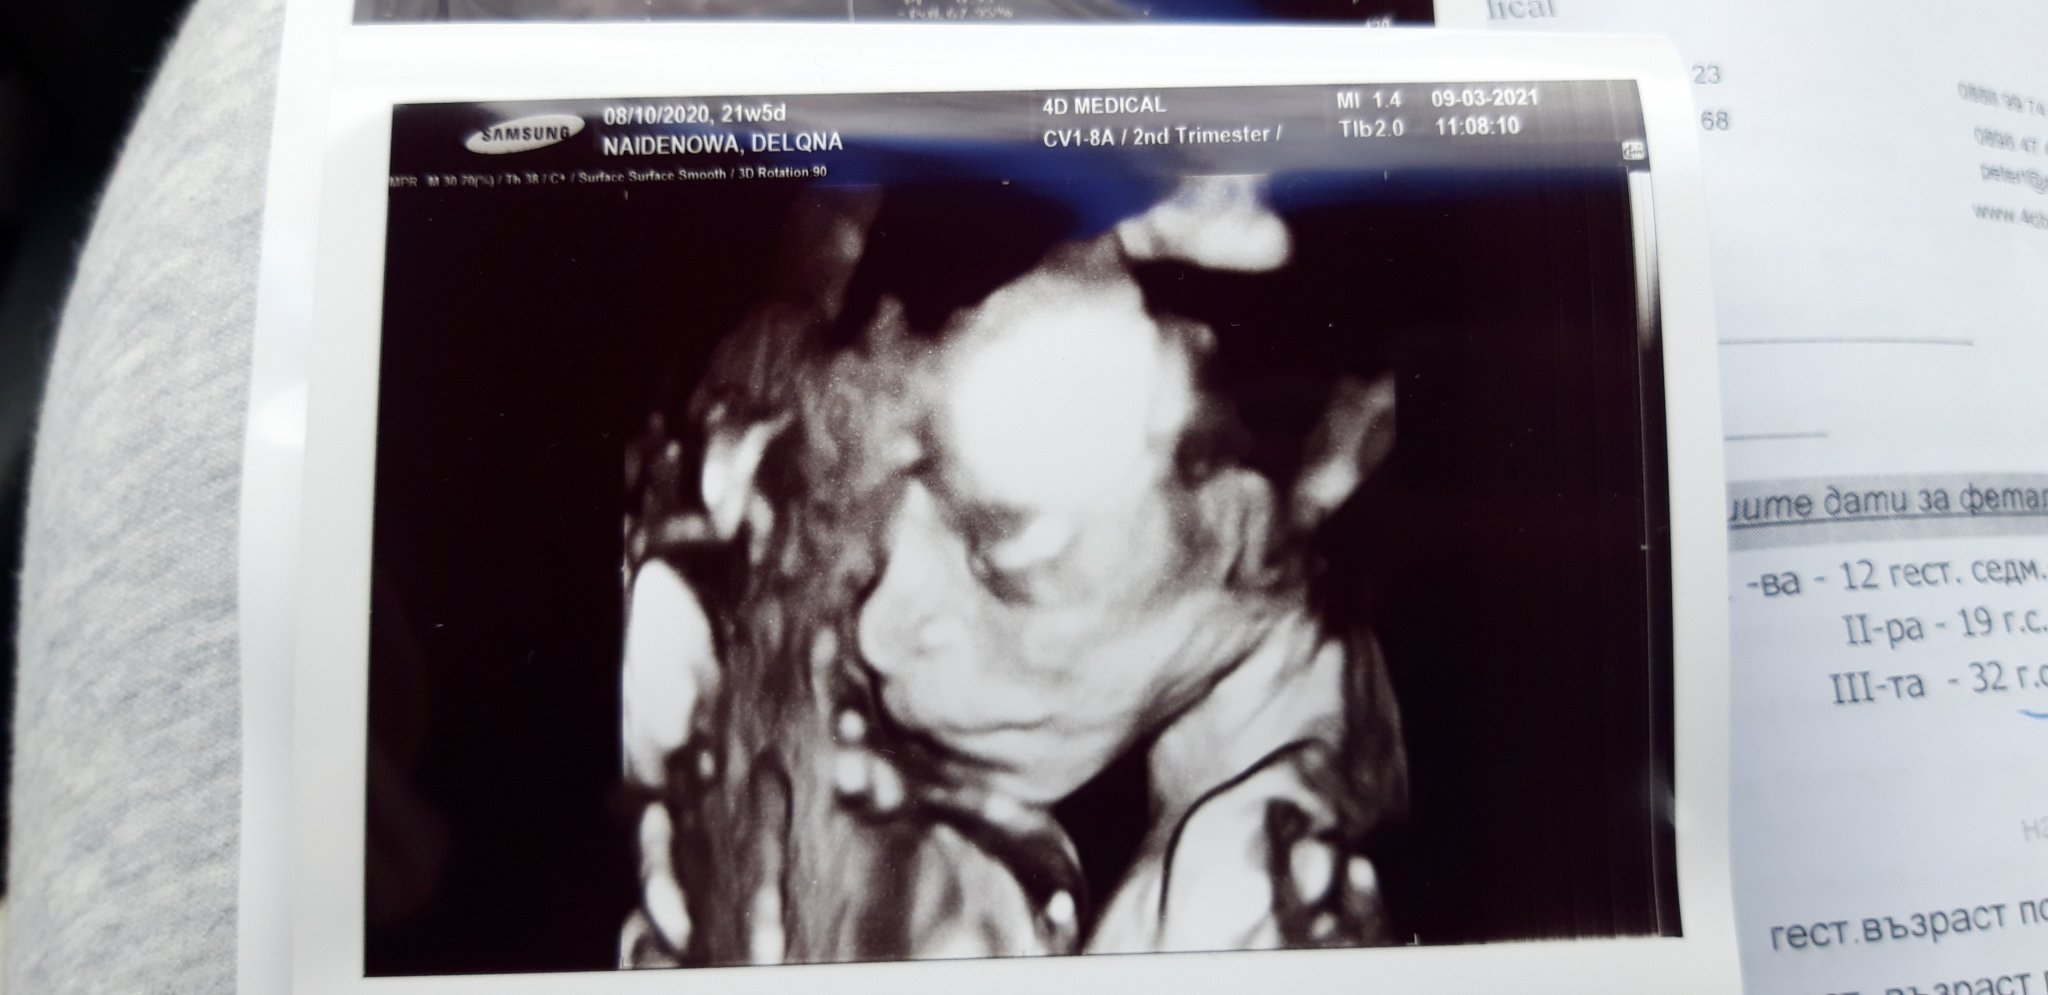

tupunger42020 то па една хубава снимка... Grinning пак не се вижда на 100%, обаче да, може и момченце да е, но лично аз съм 50/50 Grinning ( вкарвам смут) ето и снимчица как трябва да изглежда:

Здравейте! След дълга пауза и аз да се включа с хубави новини!

В 21+5 се водим по цикъл, но заради късна овулация каза, че размерите му са като за 19г.с.

Каза, че няма никакъв проблем относно здравето и растежа на юнака, само ще има, ако планирам секцио и лекарите не знаят за това(това бяха думите му). Тежим 442 гр. и сме дълги 25см, много активно бебе, усещам го почти цял ден и през нощта също като ставам до тоалетна или като се събудя то вече рита и си прави акробатичните номера. Видяхме му личицето(не допуснаха таткото на прегледа, но имаше диск с целия преглед на ехографа с меренията му и с всичкото му общо взето), установихме, че е доста смесенко Smile , но нослето е моето Blush Heart и ще има същите бузки като меннн, а устичката му е смесена между на двамата Grinning Hug

Много съм щастлива, успокоих се, че всичко е наред и така!

Извинявам се за мнооого дългия пост иначе Grin Smile и да ви покажа бебчоо също Heart